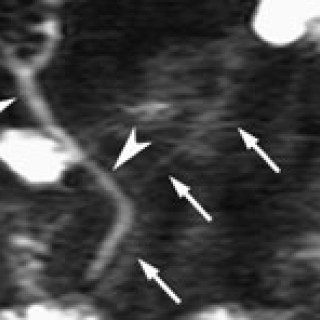

Pasientar med akutt innsetjande brystsmerter er ei stor diagnostisk utfordring. Symptomet kan oftast tilskrivast kardiovaskulære, pulmonale, muskel- og skjelettopphavelege eller psykiske lidingar, men tilstandar i gastrointestinalkanalen kan o†g gje opphav til dette symptomet. Spontan oesophagusruptur, også kalla Boerhaaves syndrom, er ei høgst uvanleg årsak til akutte brystsmerter. Pasienten . Mann, fødd i 1912, budde heime og hadde tidlegare stort sett vore frisk, men fekk i 2000 innlagt permanent kateter pga. urinretensjon. Ein dag i april 2001 då han skulle ete middag, fekk han akutt...